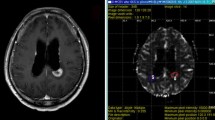

High spatial resolution of dynamic contrast-enhanced (DCE) MR imaging allows characterization of heterogenous tumor microenvironment. Our purpose was to determine which is the best advanced MR imaging protocol, focused on additional MR perfusion method, for predicting recurrent metastatic brain tumor following gamma-knife radiosurgery (GKRS).

Seventy-two consecutive patients with post-GKRS metastatic brain tumor were enrolled. Two readers independently calculated the percentile histogram cutoffs for normalized cerebral blood volume (nCBV) from dynamic susceptibility contrast (DSC) imaging and initial area under the time signal-intensity curve (IAUC) from DCE imaging, respectively. Area under the receiver operating characteristic curve (AUC) and interreader agreement were assessed.

For differentiating tumor recurrence from therapy effect, adding DCE imaging to diffusion-weighted imaging (DWI) significantly improved AUC from 0.79 to 0.95 for reader 1 and from 0.80 to 0.96 for reader 2, respectively. There was no significant difference of AUC between the combination of DWI with DSC imaging and the combination of DWI with DCE imaging for both readers. With the combination of DWI and DCE imaging, the sensitivity and specificity were 86.7 and 88.1 % for reader 1 and 90.0 and 85.7 % for reader 2, respectively. The intraclass correlation coefficient (ICC) between readers was highest for calculation of the 90th percentile histogram cutoffs for IAUC (ICC, 0.87).